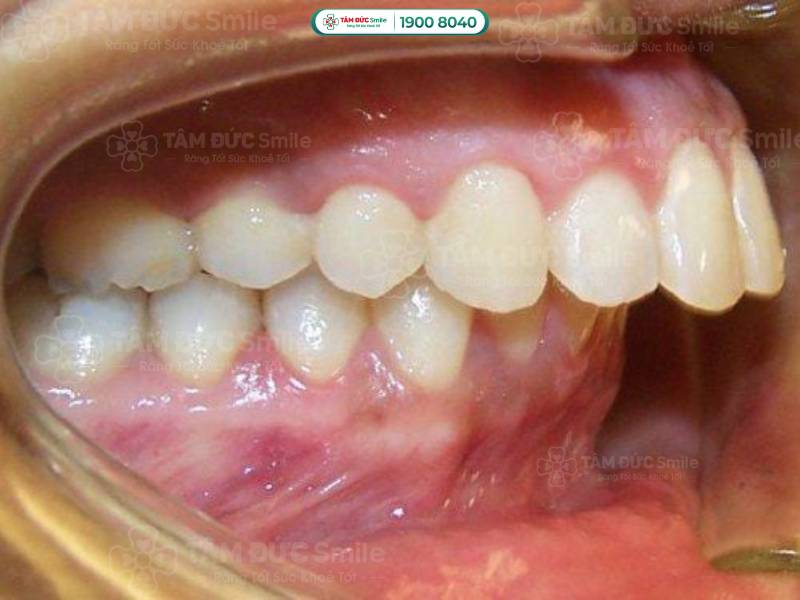

Khớp cắn sâu là tình trạng sai lệch cấu trúc răng và xương hàm. Khi đó, hàm dưới bị lệch về phía sau so với hàm trên và bị hàm trên che khuất.

- Hàm dưới bị lệch về phía sau so với hàm trên, hình thành một khoảng cách giữa răng trên và răng dưới.

- Răng hàm dưới bị răng hàm trên che khuất. Răng hàm dưới có thể chạm vào phần nướu trong của răng hàm trên.

- Dáng mặt không hài hòa, lộ nhiều răng cửa trên, đôi khi không nhìn thấy răng cửa dưới.

Khớp cắn sâu là tình trạng hàm dưới bị lệch về phía sau so với hàm trên và bị hàm trên che khuất